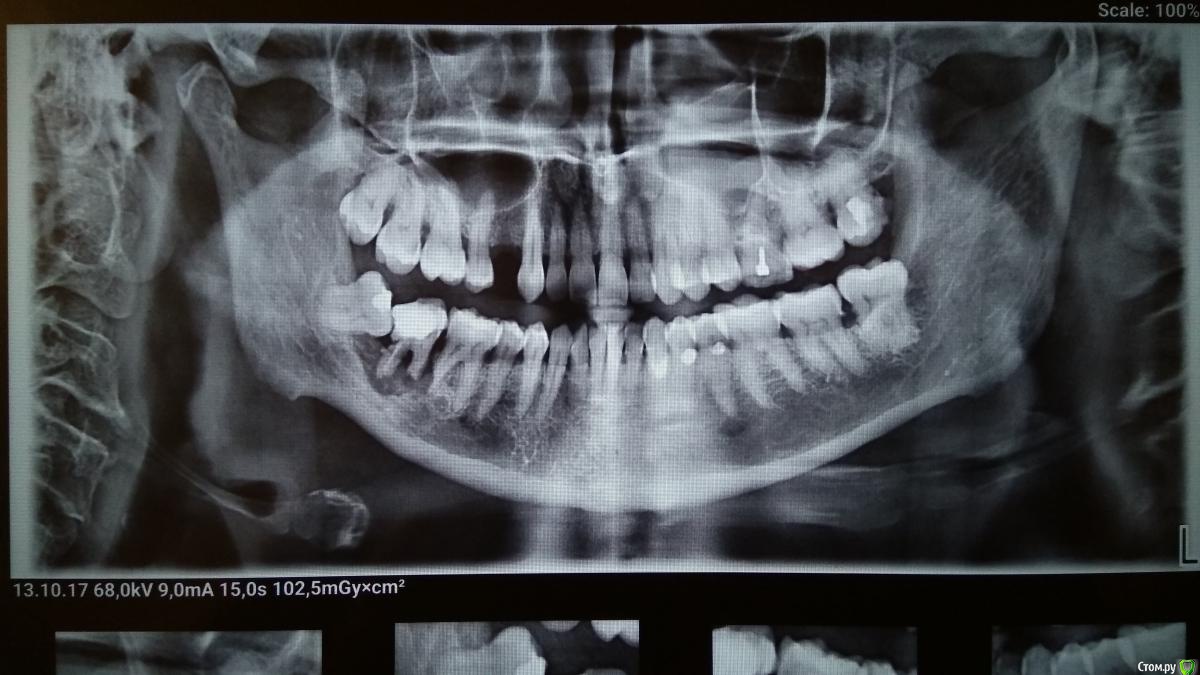

Андре931 Опубликовано 13 октября, 2017 Поделиться Опубликовано 13 октября, 2017 Добрый вечер уважаемые доктора! Прокомментируйте пожалуйста снимок.Врач стоматолог настаивает на удалении 48,47,46 зубов. Насколько справедливо такое заключение? Возможно ли лечение?Какие ещё проблемные зубы присутствуют на снимке? Ссылка на комментарий

DmitrySH Опубликовано 13 октября, 2017 Поделиться Опубликовано 13 октября, 2017 Благодарю за ответ. Можно чуть подробнее о причинах к удалению 46? Возможно ли сохранение?Отсутствие кости дистально, резорбция дистального корня. Удаляйте. 1 Ссылка на комментарий

IvanK Опубликовано 16 октября, 2017 Поделиться Опубликовано 16 октября, 2017 Нужно наладить гигиену, убрать поддесневые зубные отложения согласен с коллегами - все 8ки - удаление + 47, 46 - себе бы я не торопился удалять, но надо понимать, что это возможный исход. имплантация 14, повторное лечение с последующим протезированием 26 Ссылка на комментарий